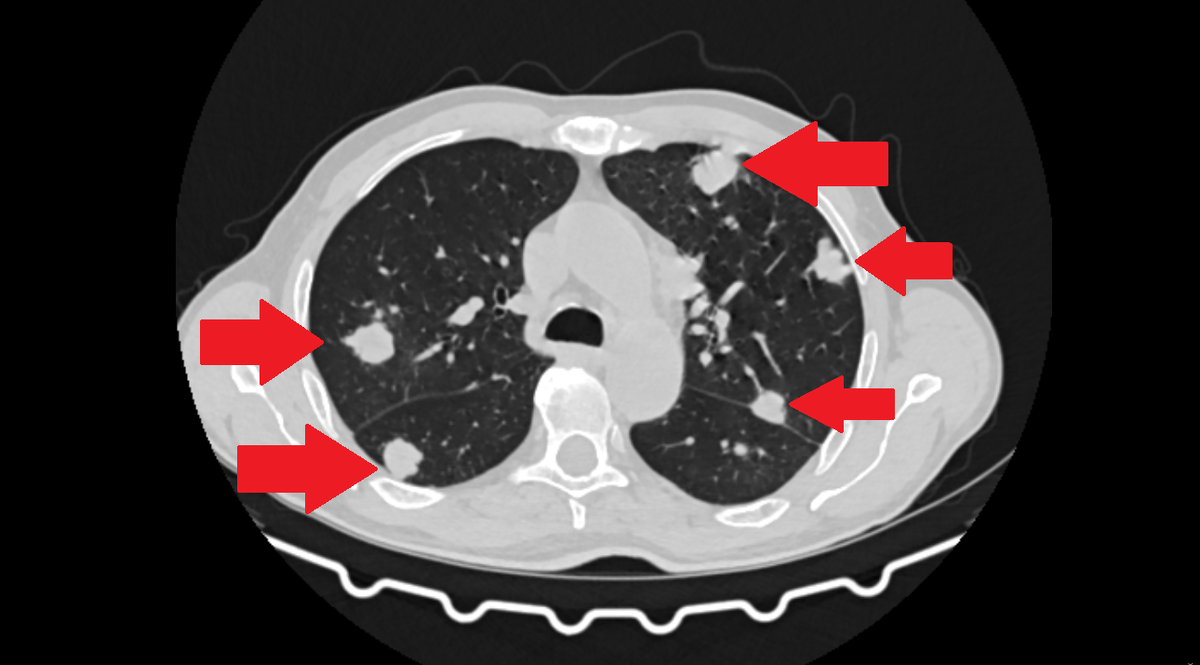

Множественное метастатическое поражение легких. Компьютерная томография.